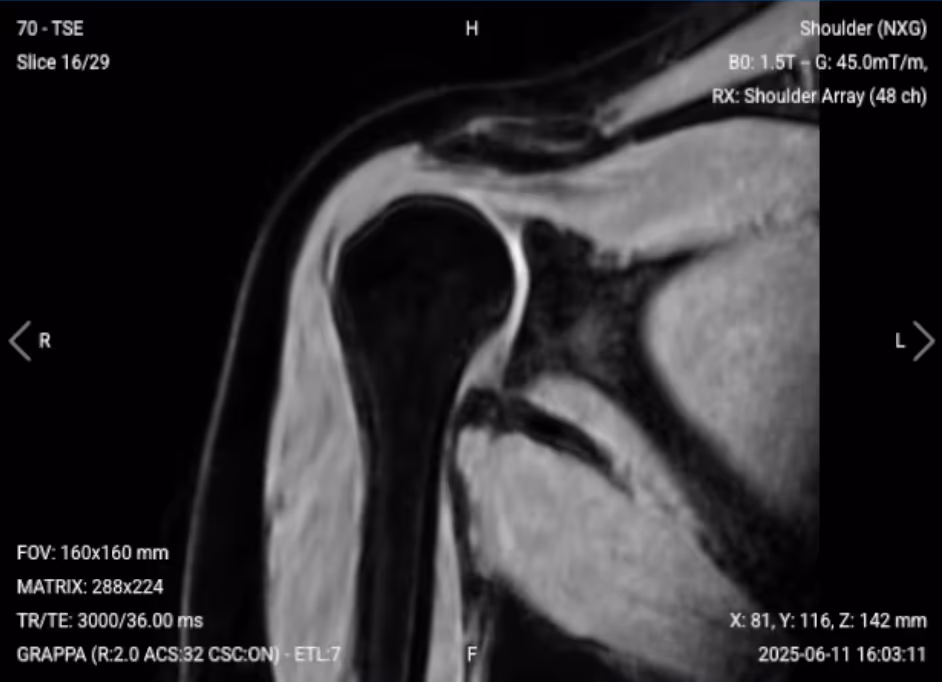

T2-weighted imaging makes fluids appear bright. This contrast is ideal for detecting tissues and abnormalities with high water content.

In shoulder MRI, T2 sequences help confirm pathology seen on other sequences and distinguish real inflammation from magic angle artifacts. They are particularly useful for evaluating edema, inflammation, joint effusions, and confirming whether increased signal on other sequences represents true pathology.

✅ Coronal T2 of the Shoulder – Correct Image Example:

Things to Look for in Coronal T2: